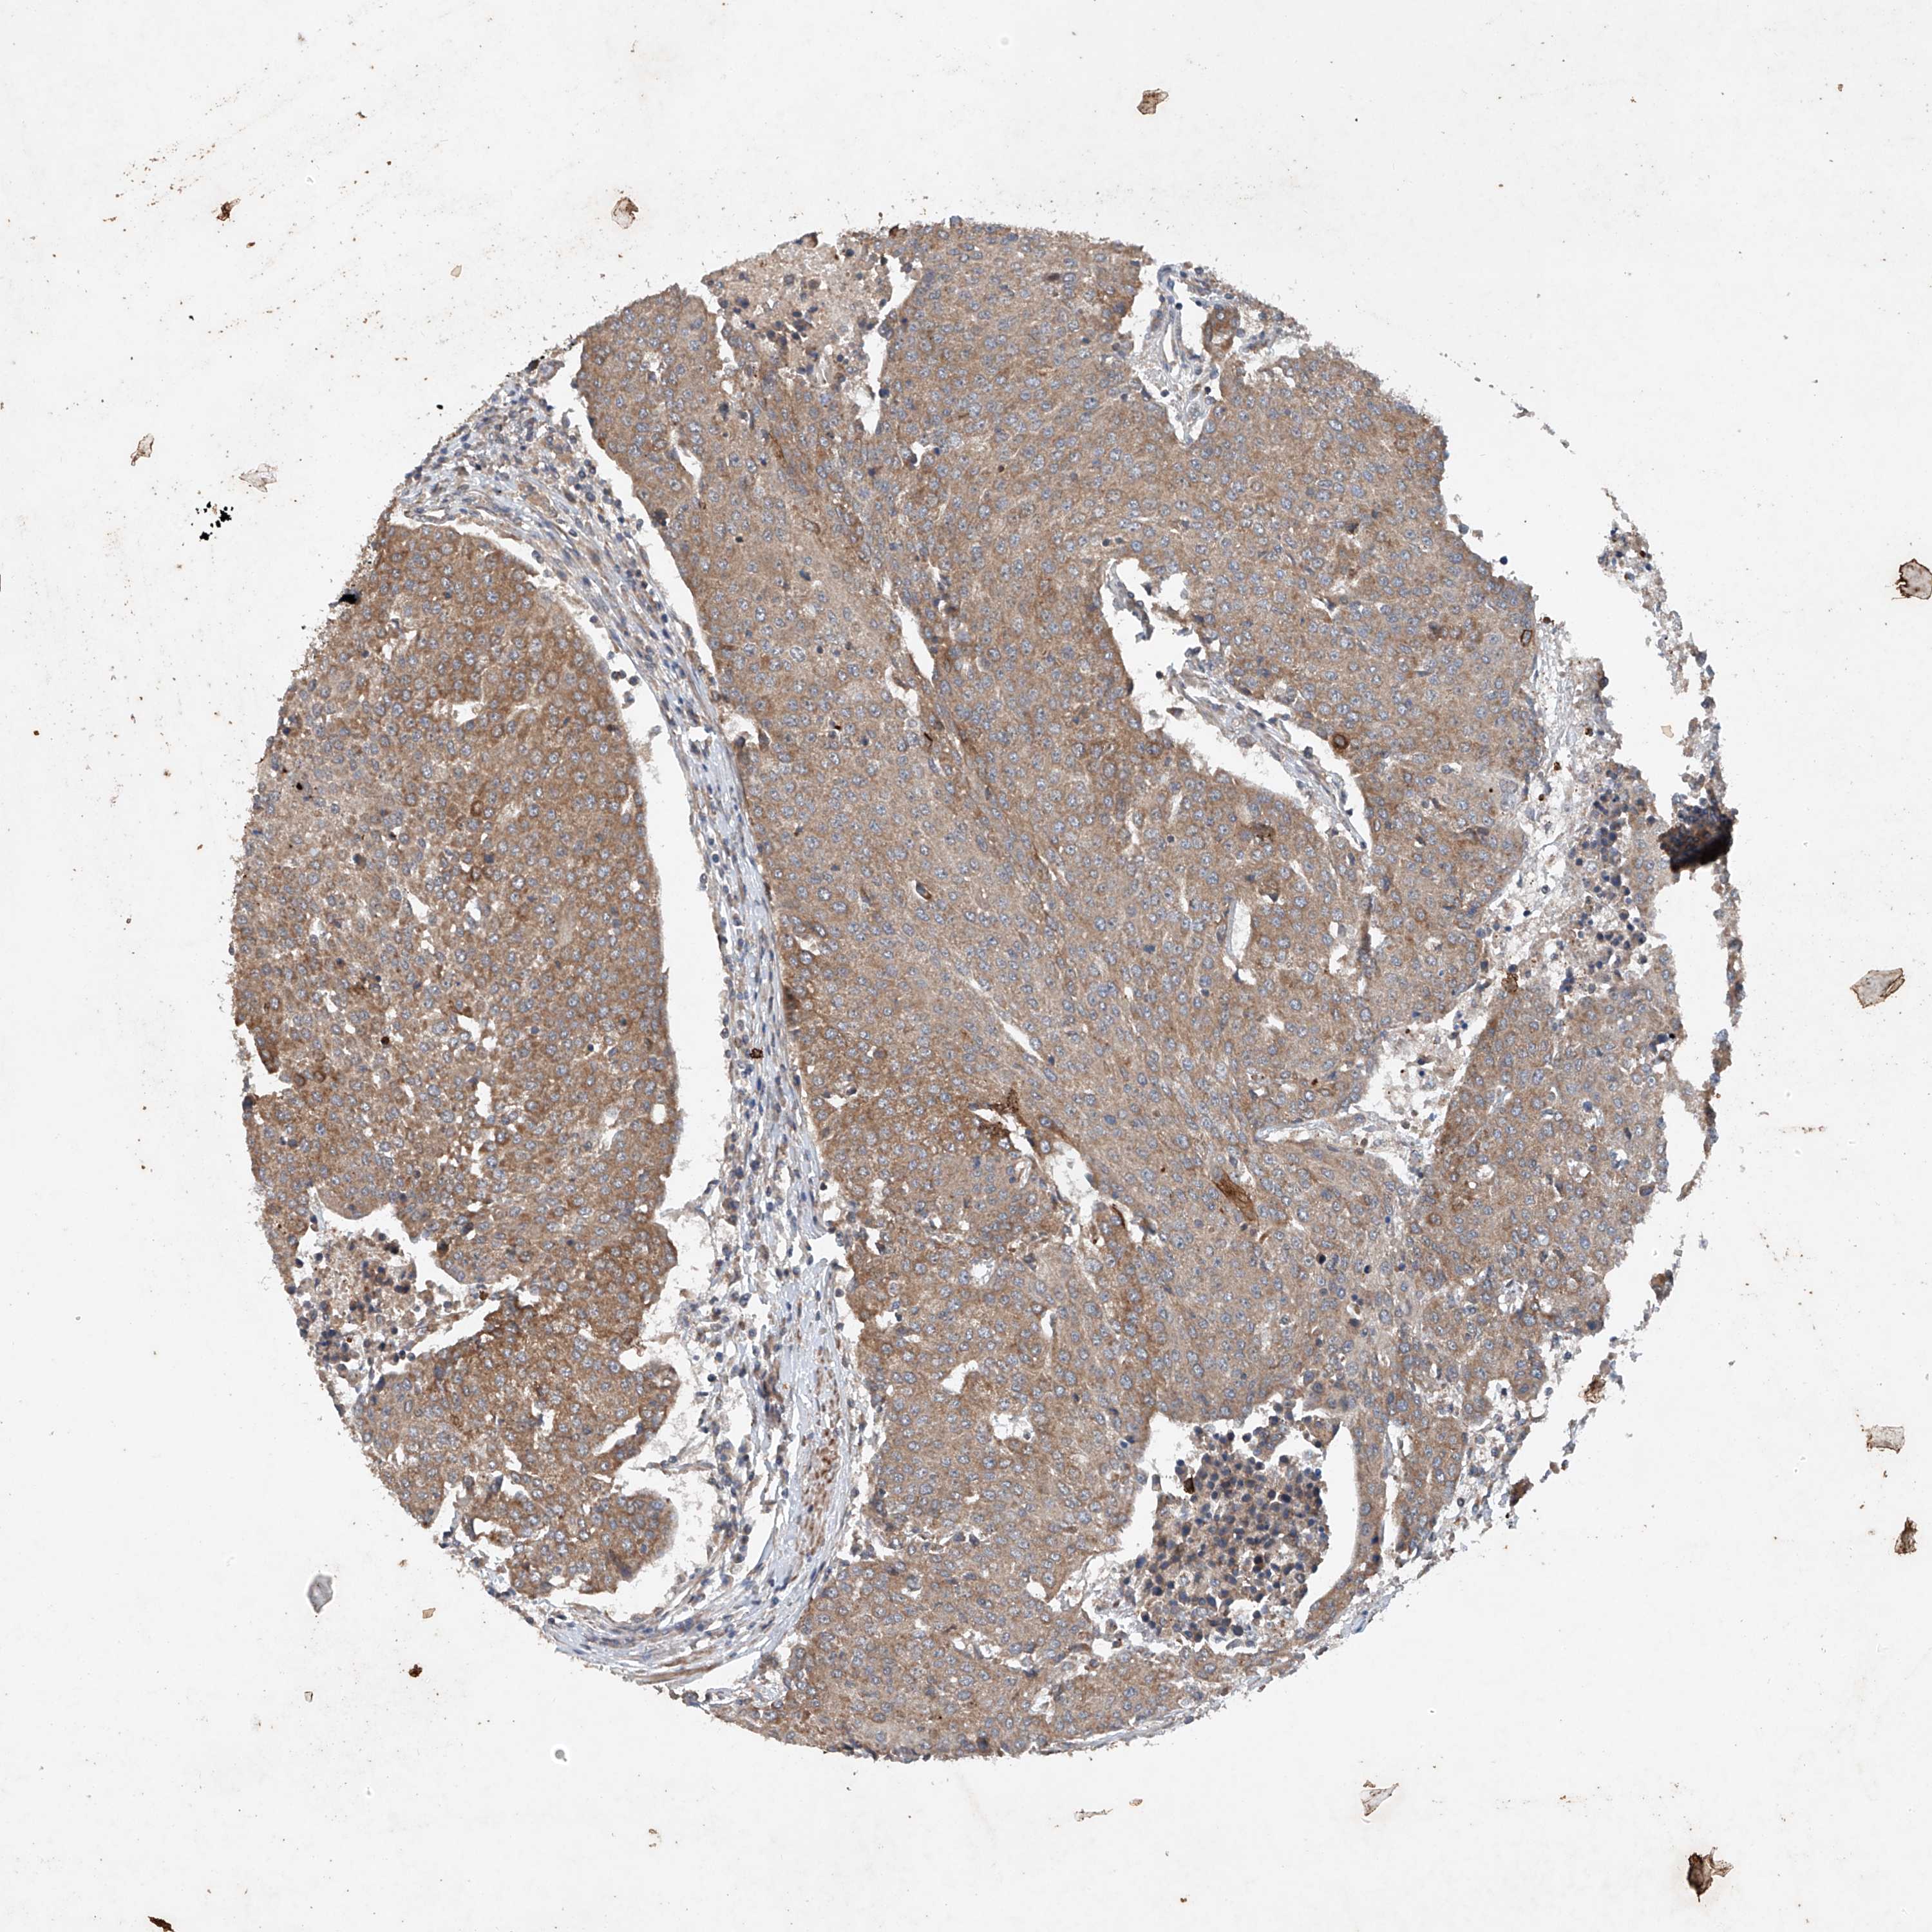

UROTHELIAL CANCER - Protein expressioni

A mouse-over function shows sample information and annotation data. Click on an image to view it in a full screen mode. Samples can be filtered based on level of antibody staining by selecting one or several of the following categories: high, medium, low and not detected. The assay and annotation is described here.

Note that samples used for immunohistochemistry by the Human Protein Atlas do not correspond to samples in the TCGA dataset.

Antibody stainingi

Antibody staining in the annotated cell types in the current human tissue is reported as not detected, low, medium, or high, based on conventional immunohistochemistry profiling in selected tissues. This score is based on the combination of the staining intensity and fraction of stained cells.

Each image is clickable and will lead to virtual microscopy that enables deeper exploration of all samples and also displays staining intensity scores, fraction scores and subcellular localization as well as patient and tissue information for each sample.

Antibody HPA029137

Antibody HPA029138

Antibody HPA029139

Staining

High

Medium

Low

Not detected

Intensity

Strong

Moderate

Weak

Negative

Quantity

>75%

75%-25%

<25%

None

Location

Nuclear

Cytoplasmic/membranous

Cytoplasmic/membranous,nuclear

Urothelial carcinoma, Low grade

Urothelial carcinoma, High grade